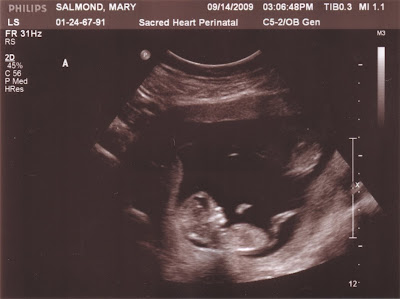

The Newest Pics

I had a referral appointment to Sacred Heart in Pensacola (45 min drive) on Monday for an 'official' ultrasound & for the first initial screenings. The Air Force base that we are stationed at has a hospital, with many things, but because I'm having twins they are taking a few extra precautions & will liberally be referring me to a Perinatalogist. Except for the drive, I don't mind because the more precautions, the better :o)

After my appointment on Thursday, and I saw & heard the heartbeats, I huge weight was lifted off my shoulders. I have been incredibly anxious since I found out I was pregnant because I didn't want to have another miscarriage, or tubal pregnancy. Sometimes I think the more you know, the worse it is!!!

This weekend I finally allowed myself to feel pregnant. I touched my stomach and thought about the babies growing inside, and I finally let Eric do the same. He was also very apprehensive because we both were so excited in March & immediately started to prepare, only to be very disappointed. But now, every time I find him on the computer he is looking at baby strollers, car seats, making lists, and we have to go to the baby section of whatever store we are in. I am floored at how excited he is & how involved he wants to be in planning every little detail.

We are still going to hold off on purchasing anything until after 20 weeks, just to be on the safe side. But, I am so grateful for all the well-wishes from everyone, it really means the world to me.

I still plan to work up until I am told not to, but I have no plans of putting myself, or the babies at any kind of risk! So, hop on & enjoy the ride as my family grows from 2 to 4 by March of next year :o)

Oh yeah...did I mention it's TWINS!!! I had my first ultrasound today, and I suspected it when my stomach started to pooch out at 9 wks, but I was losing weight because of how sick I've been.

Eric is SOOOOOOOOOOOO excited, and has the ultrasound pictures already in his ruck sack to bring to work with him in the morning.

My due date is 25 March, but twins are lucky to make it to 36 weeks, so it could be as early as February. Please continue to keep our family in your prayers!!